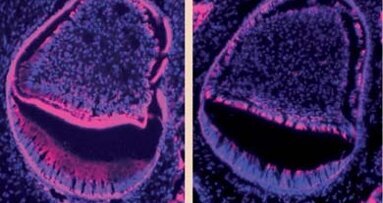

Szkliwo jest najtwardszą tkanką ludzkiego organizmu. Naukowcy z Forsyth Institute oraz z uniwersytetów w Pittsburghu i Michigan w USA udokumentowali proces, w którym powstaje ta wysoce odporna tkanka.

Przy pomocy mikroskopu krioelektronowego odkryli oni, że amelogenina – regulatorowe zewnątrzkomórkowe białko macierzy, które wytwarza 20-30% młodego szkliwa może stopniowo się grupować. Następnie jej skupiska ulegają ustabilizowaniu i organizują kryształy fosforanu wapnia w równoległe warstwy, które spajają ze sobą.

W rezultacie powstają struktury mineralne w kształcie igieł, co według naukowców przypomina

złożony mikromateriał ceramiczny. Dodają oni, że konieczne są dalsze badania, które pozwolą w

pełni zrozumieć przebieg procesu. Uzyskane wyniki mogą jednak umożliwić kierowanie w podobny

sposób ułożeniem cząsteczek w warunkach laboratoryjnych w celu tworzenia nowych materiałów biomedycznych do zastosowania m.in. w stomatologii odtwórczej.